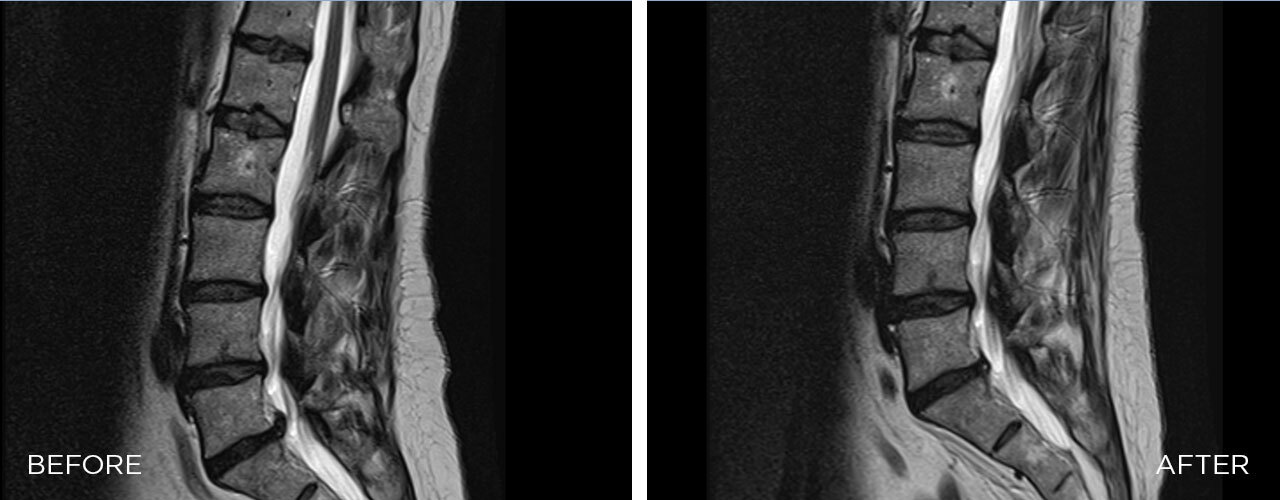

Mechanism of Action

SPINAL DECOMPRESSION is a mechanical therapy that uses automated decompressive forces to mobilise joints, relieve the pressure over neuro-spinal structures, and relax and elongate soft tissues.

Lower Back Pain

The SPINAL DECOMPRESSION promotes a new way forward to precise targeting of the therapy into impaired segments of the spine and innumerable options for the treatment of lower back pain of any origin.